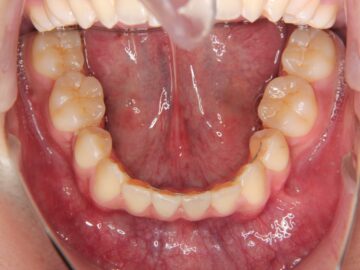

治療後

治療の詳細

| 抜歯部位 | 上顎左右測第一小臼歯、下顎左右測第二小臼歯 |

| 治療期間 |

動的治療期間 3年3か月、保定治療期間 1年7か月 保定治療継続中 |